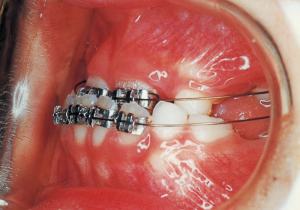

13 5-21-’90 At Phase 2 Treatment

14 6-21-’90 Beginning of second phase

15 3-23-’91 Before surgery

Pre-surgical orthodontic period: 9 months

Hospitalization period: 2 weeks

Intermaxillary fixation period: Approximately 1 month (orthodontic treatment was not possible during this period).

Post-surgical orthodontic period: 10 months